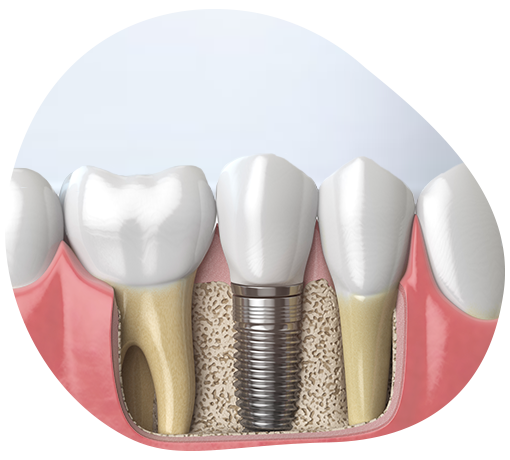

- Zubni implant menja vaš prirodni zub što znači da nećete imati više prazan prostor između zuba, a ugradnjom implanta čuvate susedne zube od brušenja, ako su oni u dobrom stanju.

- Krunica (navlaka) na implantu izgleda potpuno prirodno kao vaš zub i ima čak i veću čvrstinu što znači da nećete imati problem sa žvakanjem.

- Ugradnjom implanta sprečava se mogućnost povlačenja kosti do koje bi sigurno došlo usled gubitka zuba, jer nema stimulacije kosti, što se dešava kada zvaćete.

- Implanti su izrađeni od titanijuma. Kao takvi deluju u potpunom skladu sa organizmom. Nema alergija, nema neželjenih reakcija od strane organizma, a sve to zbog karakteristika materijala od koga su izrađeni.